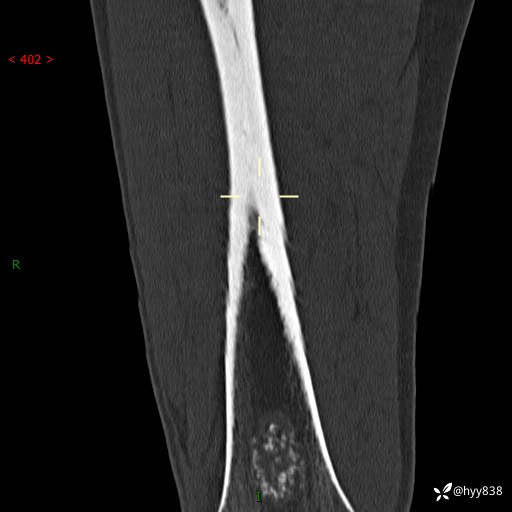

CT

img